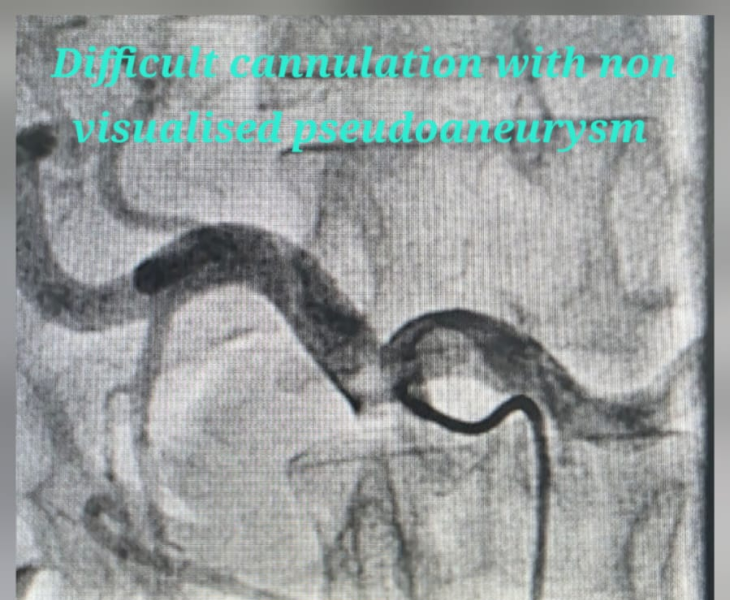

- Catheter angiography: contrast is injected to locate the pseudoaneurysm and bleeding source.

- Super‑selective catheterisation: a microcatheter is advanced into the specific branch feeding the pseudoaneurysm.